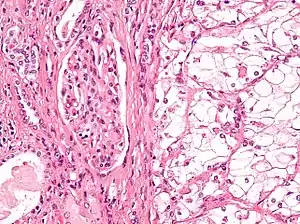

| Micrograph showing the most common type of kidney cancer (clear cell renal cell carcinoma). H&E stain. | |

The most common type of kidney malignancy is renal cell carcinoma,[33] which is thought to originate from cells in the proximal convoluted tubule of the nephron.[15][34] Another type of kidney cancer although less common, is transitional cell cancer (TCC) or urothelial carcinoma of the renal pelvis.[35] The renal pelvis is the part of the kidney that collects urine and drains it into a tube called the ureter.[35] The cells that line the renal pelvis are called transitional cells, and are also sometimes called urothelial cells. The transitional/urothelial cells in the renal pelvis are the same type of cells that line the ureter and bladder. For this reason TCC of the renal pelvis is distinct from RCC and is thought to behave more like bladder cancer.[35] Other rare types of kidney cancers that can arise from the urothelial cells of the renal pelvis are squamous cell carcinoma and adenocarcinoma.[15]

Renal cell carcinoma has been further divided into sub-types based on histological features and genetic abnormalities. The 2004 WHO Classification of the Renal Tumors of the Adults describes these categories:[39]

- Clear cell RCC